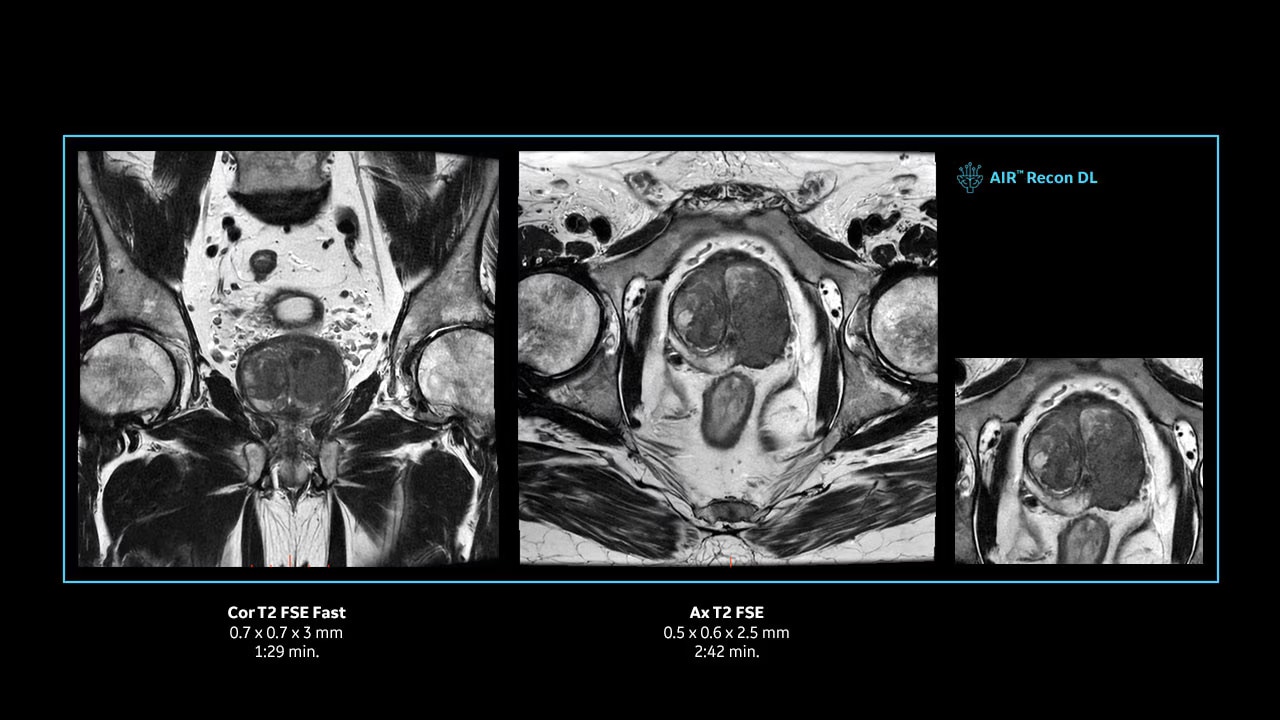

With access to the latest advanced AI technology, you can scan all anatomies and achieve pin-sharp images. Our pioneering deep learning-based reconstruction algorithm AIR Recon DL accelerates scan time and puts patients at ease.

The improved gradient of up to 80 mT/m, 200 T/m/s provides exceptional results faster and with 146 RF channels, you can ensure uniformity for every result.